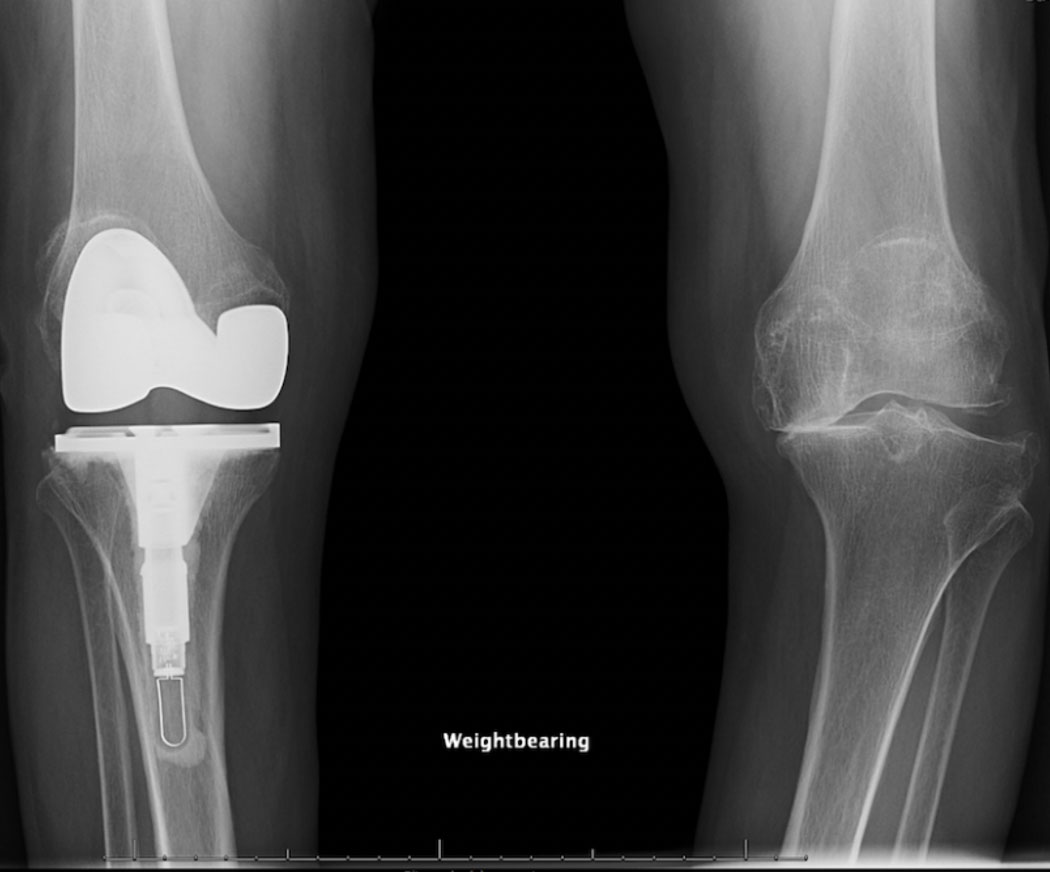

لقد تآكل الغضروف في ركبتها اليمنى، مما أدى إلى احتكاك العظام ببعضها وانحراف ساقها إلى الخارج.

أحالها طبيبها المعالج إلى جرّاحة العظام في مستشفى جامعة شيكاغو سارة والاس، الحاصلة على دكتوراه في الطب وماجستير في الصحة العامة، والمتخصصة في جراحة استبدال الركبة والورك، والتي أوصت بإجراء جراحة استبدال كاملة للركبة باستخدام زرعة متطورة.

على الرغم من أن مستشفى جامعة شيكاغو في لوس انجلس UChicago Medicine يُقدم مجموعة واسعة من الزرعات لمرضى جراحة استبدال الركبة، فقد اختارت غاميرو زرعة الركبة الذكية Persona IQ التي توفر إمكانيات مراقبة متقدمة. هذا الجهاز، الحاصل على موافقة إدارة الغذاء والدواء الأميركية، مُزوّد بمستشعرات تجمع بيانات الحركة – بما في ذلك مدى حركة الركبة أثناء المشي وطول خطوة المريض – والتي يتم إرسالها بشكل آمن إلى منصة سحابية متوافقة مع معايير HIPAA. يمكن للأطباء استخدام هذه البيانات لمتابعة مدى تعافي الركبة عن بُعد، كما يمكن للمرضى الوصول إلى بياناتهم عبر تطبيق خاص، بل ومقارنة مدى تعافيهم مع مرضى آخرين.

خلال العملية، أعادت الدكتورة والاس تشكيل نهايتي عظم الساق والفخذ لدى غاميرو، واستبدلت العظم والغضروف المتآكلين بالزرعة.